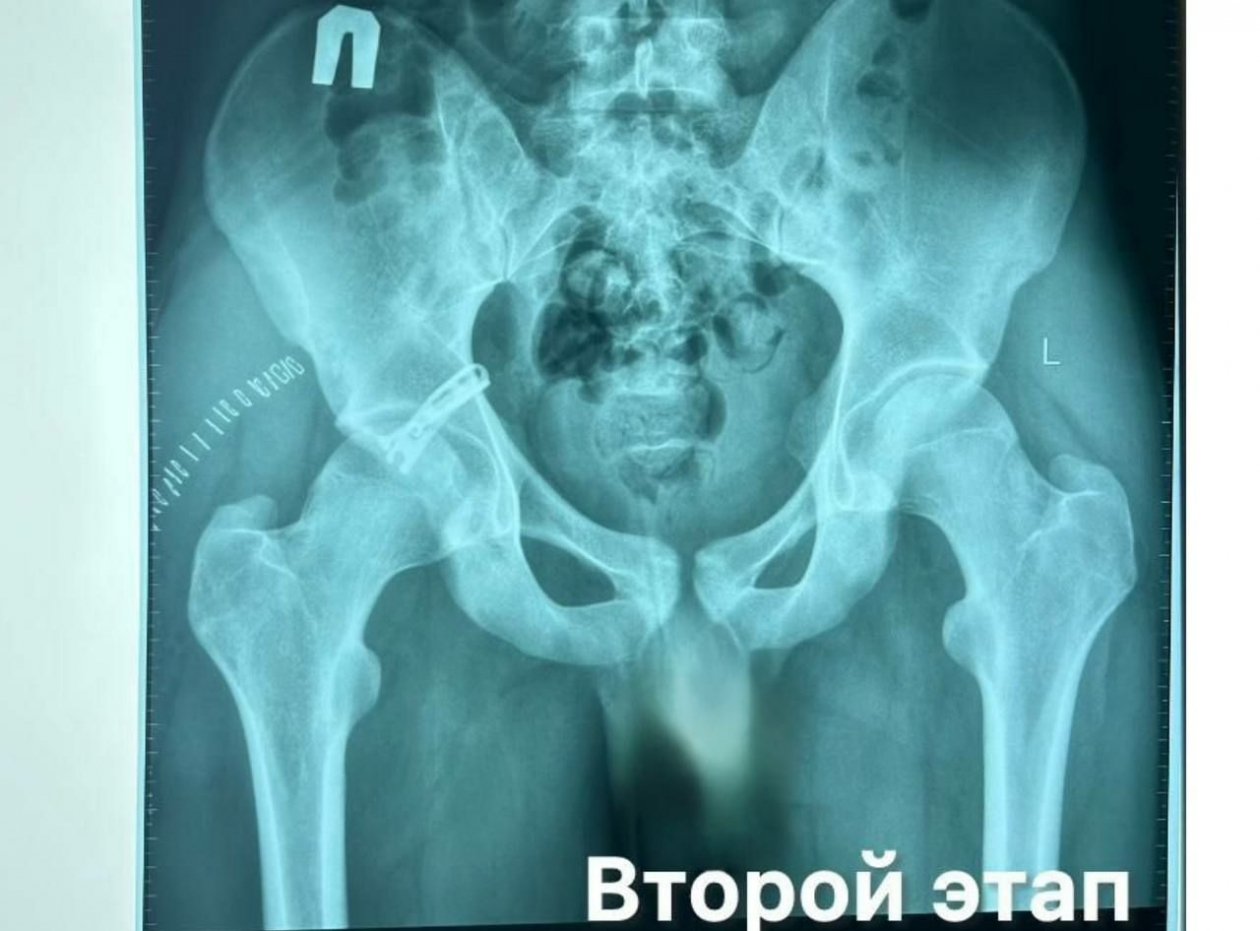

"При поступлении был поставлен диагноз: вывих правого тазобедренного сустава с переломом вертлужной впадины — серьёзнейшая травма, которая не имеет ничего общего с привычным выражением "сломал ногу". Вертлужная впадина является ключевой частью тазобедренного сустава — сложного "шарнира", обеспечивающего движение, способность стоять, ходить и держать равновесие", — говорится в сообщении.

Врачи сначала выполнили закрытое вправление вывиха, а затем провели сложную операцию по фиксации фрагмента вертлужной впадины с использованием винта и пластины.